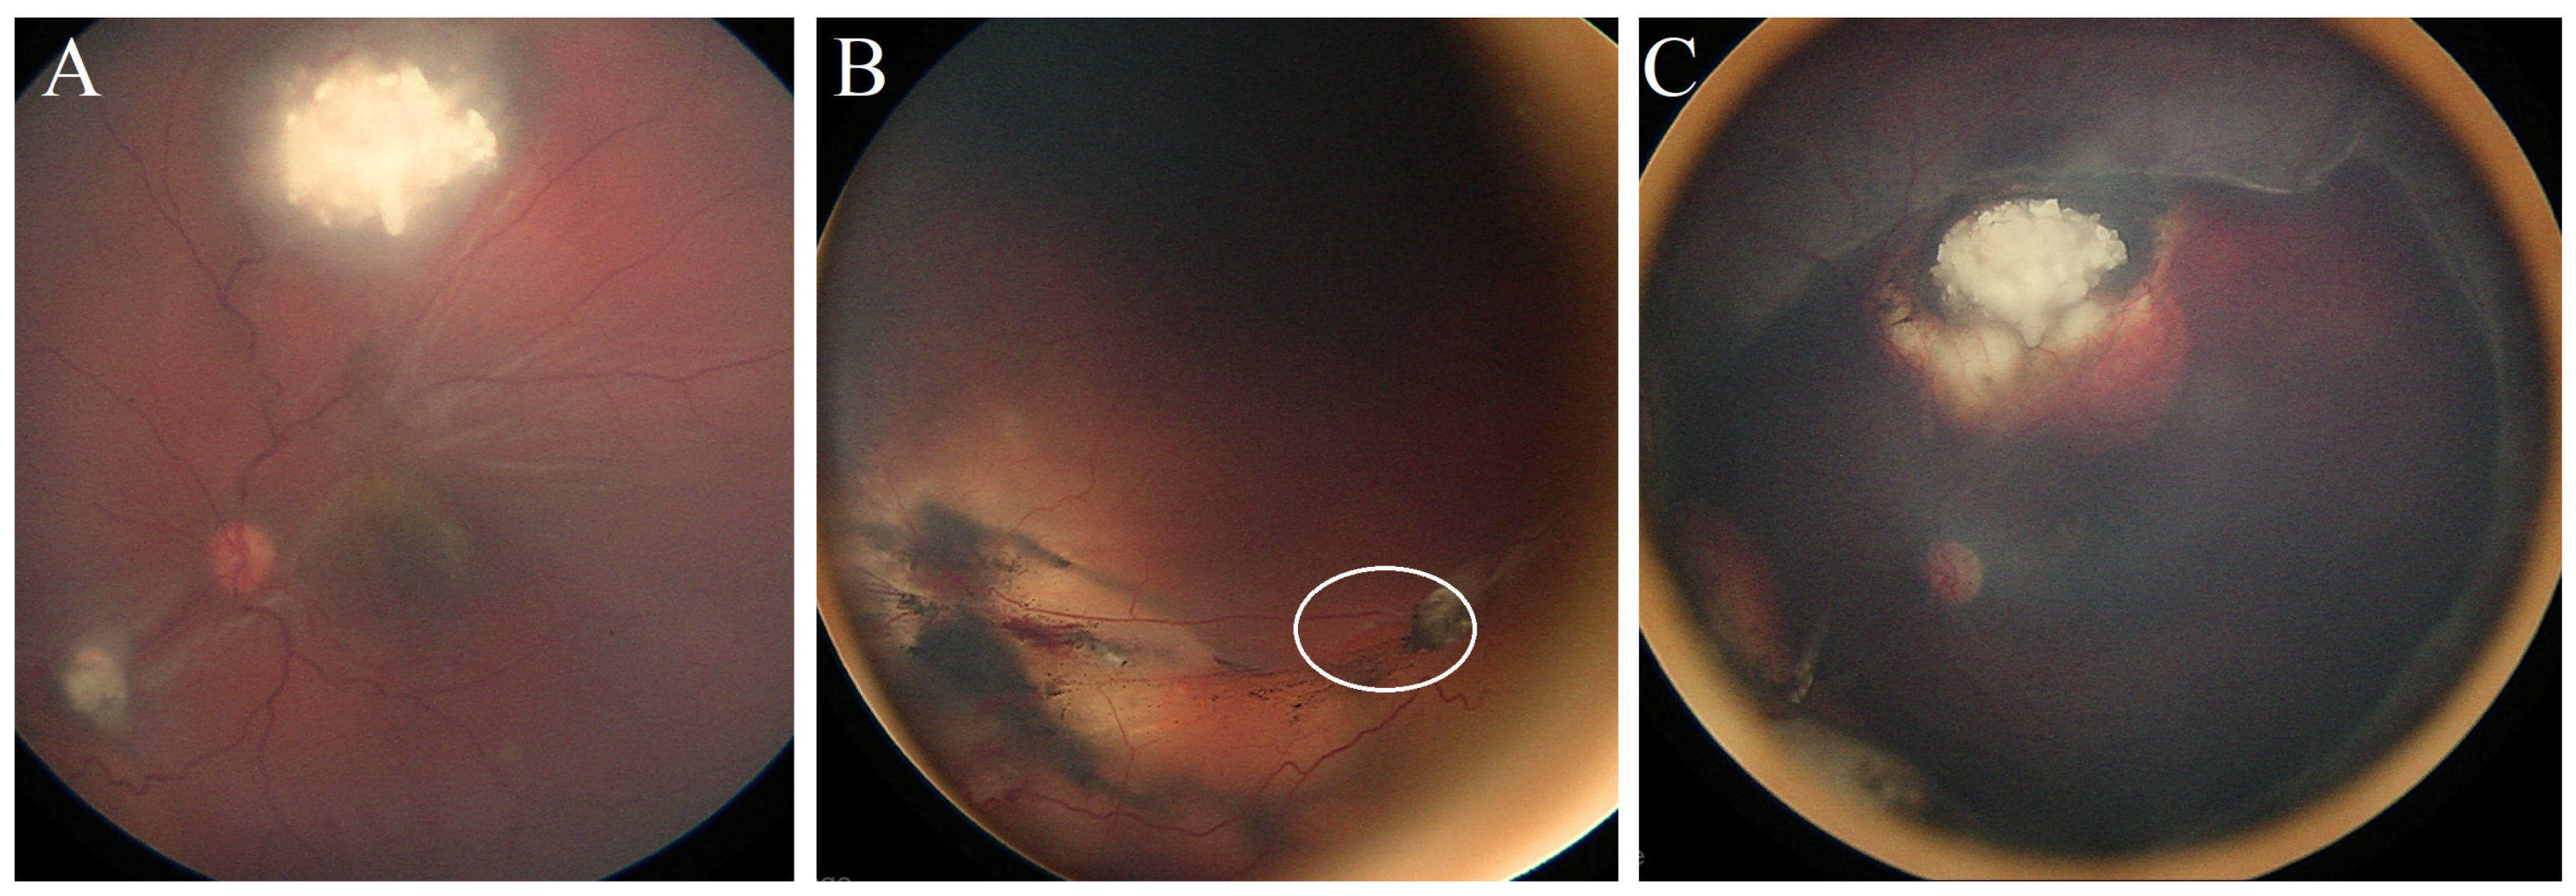

Case #2: A 3-year-old boy was diagnosed with Rb in both eyes. Prior to being referred to our center, his right eye underwent enucleation, while his left eye received five cycles of systemic chemotherapy without focal therapy (three cycles of Carboplatin/Etoposide and two cycles of Cyclophosphamide/Vincristine). Upon arrival at our center, the left eye exhibited three active retinal tumors, each partially calcified with surrounding vitreous seeds. Treatment included transpupillary thermotherapy (TTT) laser, cryotherapy, and subtenon carboplatin injection.

Four weeks after the fourth subtenon injection, he developed subtotal RRD, and a retinal break was identified at the margin of the calcified superior tumor (

Figure 1A). Scleral buckling and retinopexy of the retinal break were implemented for retinal repair. The retina was reattached within three weeks, and the remaining retinal tumors were treated with four further TTT sessions (

Figure 1B). Over an eight-year follow-up period post-surgery, there has been no evidence of tumor reactivation or metastases, and the patient’s best corrected visual acuity was 6/12 at the most recent examination.